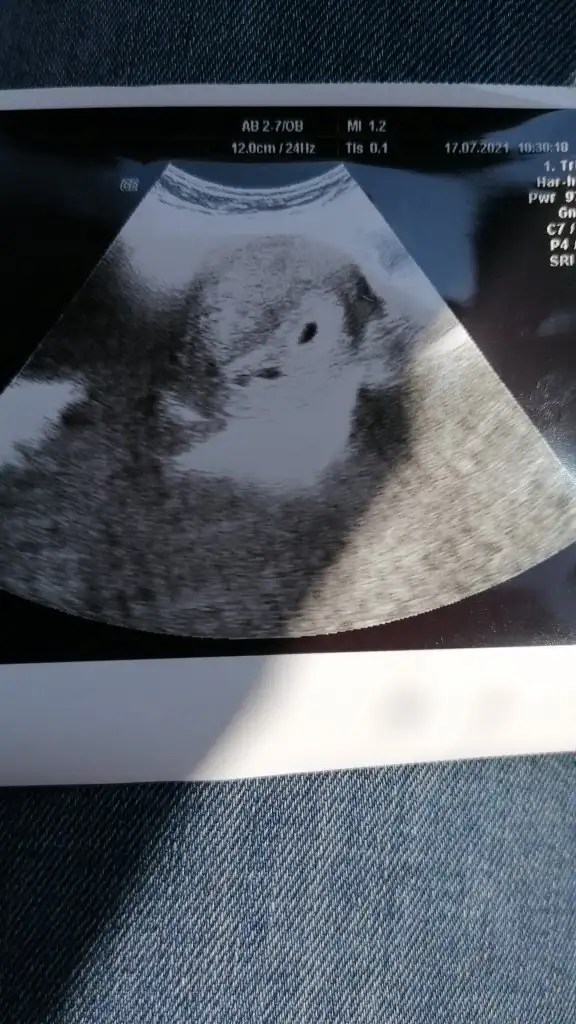

Merhabalar herkese. Yeni haberler alan herkese hayırlı olsun 🙏🤗 Dün 5+0 Ken sıkışıkbir şekilde Dr a gittim keseyi gördü çok şükür bir sıkıntı da yok dedi. Ama iki tane kese görünüyor ikiz olabilir dedi emin olmak için 15 gün sonra tekrar çağırdı. Böyle olup da olan ya da olmayan var mı acaba 15 gün nasıl dayanavağım 🙈🤗

• IMG-20210717-WA0000.webp

IMG-20210717-WA0000.webp

57,4 KB · Görüntüleme: 123

Bence de iki kese :)) maaşallah. 4+3 te benim böyle görünmüştü. Aynen devam ediyoruz şimdi biri 9+3 diğeri 9+2. Inşallah gönlüne göre olsun 15 gün sonra kalp atışını bile duyarsın

hayırlı olsun. insallah saglikli sihhatli kucagina alirsin. benim ilk gebeligimde iki kese gözüktü fakat ilerleyen haftalarda bir tanesi kalp atisini duymadan kendiliginden küçülüp kayboldu. bu gebeligimde de bir kese gördük. kalp atışı icin 6. haftadda bakildiginda iki kese iki kalp gördük. her sey nasip. benim tecrubem kalp atışı duymadan kimseye bisey söylememek oldu.